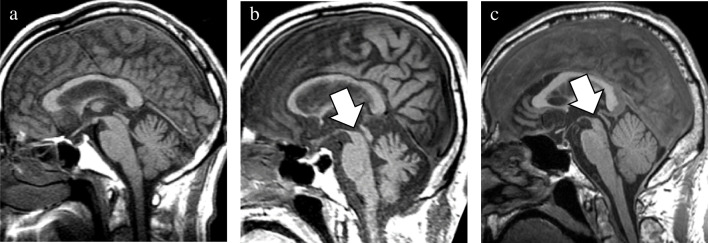

In addition to the well-established GCA and MTA scales, newly devised rating scales were utilized to evaluate the presence of midbrain atrophy and asymmetric atrophy. The degree of midbrain atrophy was assessed using a three-point scale (0 = normal, 1 = mild, and 2 = severe) primarily on sagittal T1WIs (Fig. 1). Mild midbrain atrophy indicated a slight reduction in the anteroposterior and/or superoinferior diameters. By contrast, a definitive decrease in these diameters was classified as severe midbrain atrophy. The degree of asymmetry in the frontal, temporal, parietal, and occipital lobes, along with the cerebral peduncle, was assessed using a three-point scale (0 = normal, 1 = mild, and 2 = severe) on axial T1WIs (Fig. 2). Severe asymmetry indicated the definite dilation of the sulcus and/or narrowing of the gyrus between the two hemispheres. Conversely, a case with unremarkable asymmetry was rated as mild.